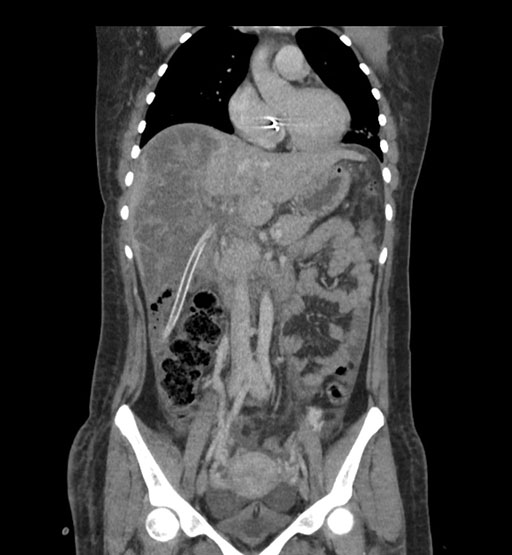

Coronal Arterial

Coronal Venous